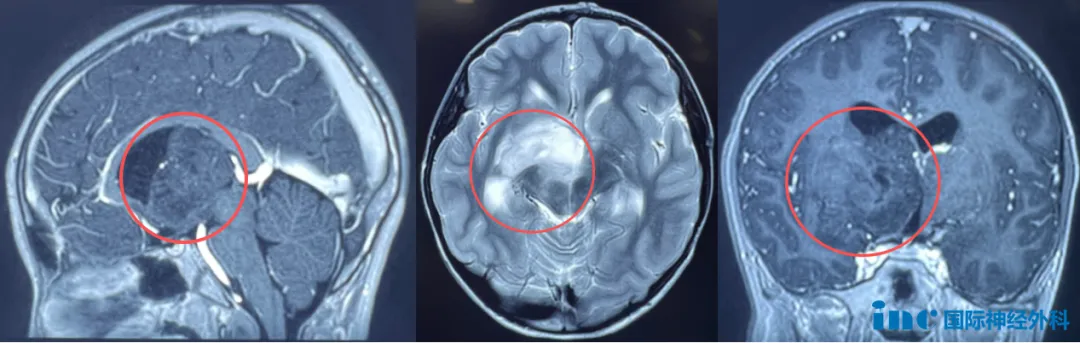

8岁男性患儿小航确诊右侧丘脑-基底节区巨大肿瘤。肿瘤位置深在、累及重要功能区,本次手术面临六大严峻风险:运动功能、感觉功能、视觉功能、记忆功能可能受损,下丘脑内分泌调节及重要血管结构同样面临挑战。此次手术是对主刀医生技术、医疗设备及团队配合的极致考验。

患儿小航,右侧丘脑-基底节区出现占位性病变,肿瘤呈弥漫性生长趋势,脑室扩大,脑脊液循环已受影响。所幸目前未出现严重症状,仅偶发记忆力下降、注意力不集中和饮水呛咳。